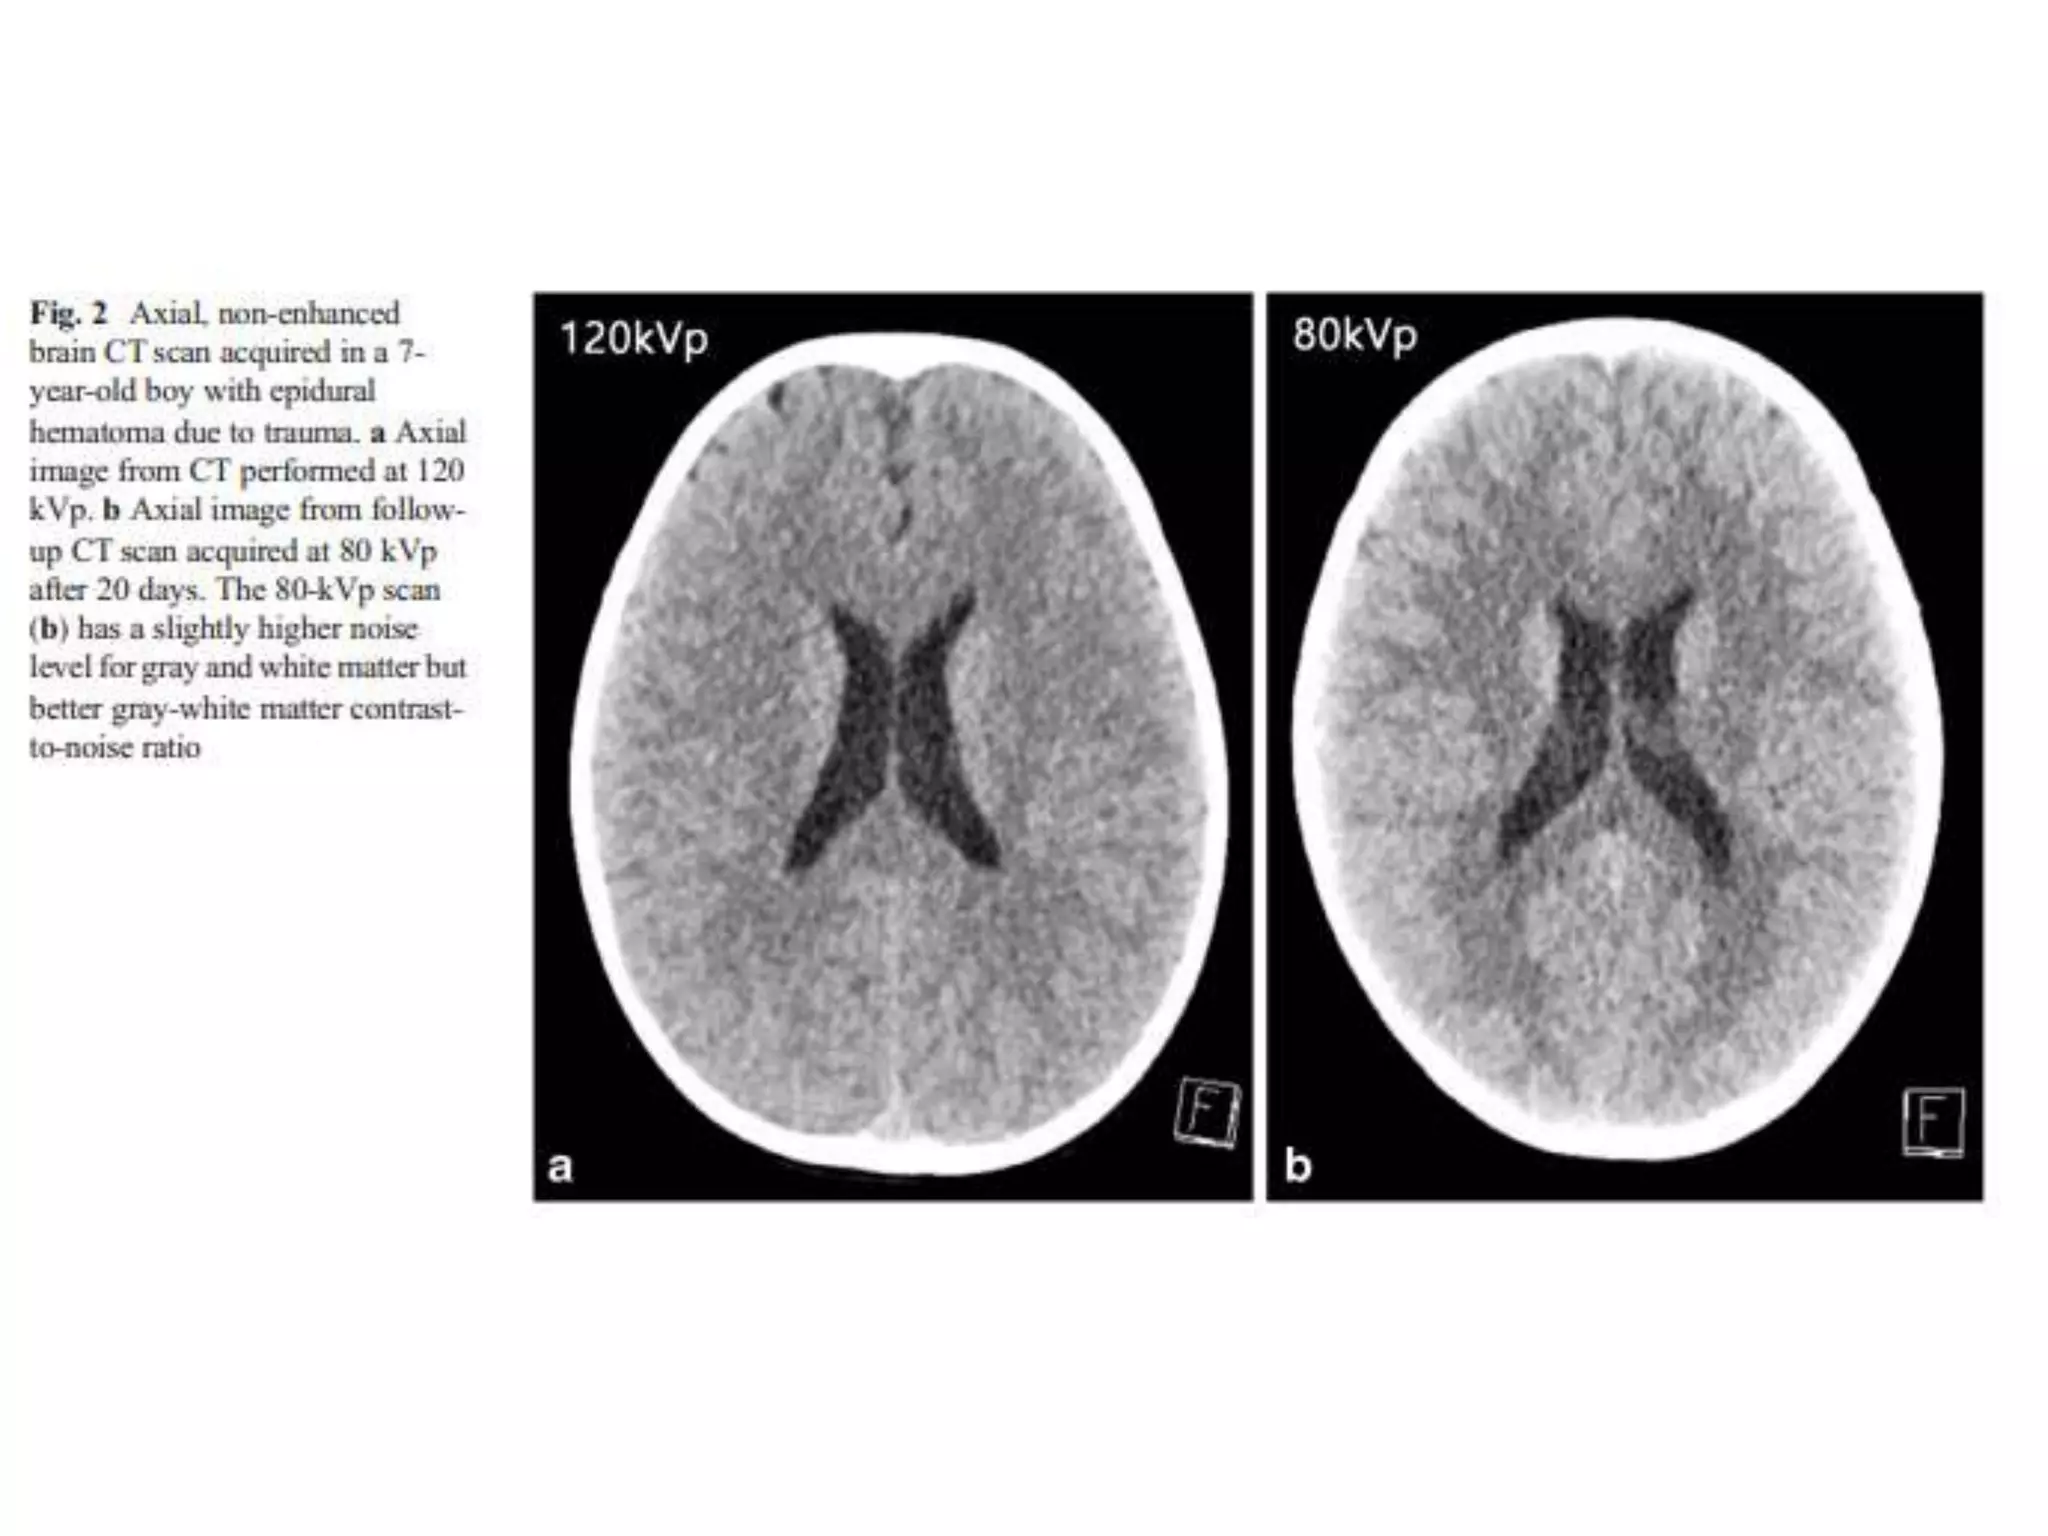

• 80 kV brain CT

– were shown to be with improved gray

matter-white matter contrast-to–noise ratios.

– Similar overall image quality

• 6.5% radiation dose reduction

• 80 kV brain CT can be an acceptable

technique to replace a standard 120 kV

CT scan in children

Conclusion • 80 kVbrain CT – were shown to be with improved gray matter-white matter contrast-to–noise ratios. – Similar overall image quality • 6.5% radiation dose reduction • 80 kV brain CT can be an acceptable technique to replace a standard 120 kV CT scan in children